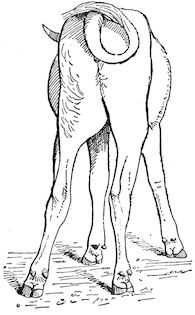

Fig. 2.—Horse suffering from osseous cachexia.

2. The second phase is characterised by more precise signs, which become almost pathognomonic. Difficulty in rising is added to the already existing tendency to remain lying, and to the interference with movement.

When lying down the patient no longer responds to the trifling stimulus, which a healthy animal needs to cause it to rise. It remains languid and apparently lazy, though in reality it experiences pain and difficulty on attempting to get up. The least muscular effort when lying down often causes it to moan, as do efforts to change its position or to walk. Even when standing still, it may appear to be in pain, and patients often assume a position similar to that of a horse suffering from laminitis.

At the end of this second phase, swellings appear, due to synovitis or arthritis of the extremities, synovitis of the sesamoid or navicular sheaths or to inter-phalangeal arthritis or arthritis of the fetlock joint. Weakness becomes marked, and the appetite is very irregular.